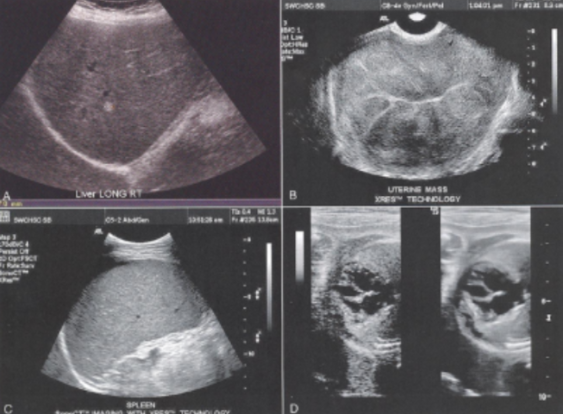

Speckle

The granular appearance of images that is caused by the interference of echoes from the distribution of scatterers in tissue.

The generation of this artifact can be compared to throwing a handful of marbles into a pond. Each marble generates a circular propagating wave. These waves combine together through the effects of constructive and destructive interferences.

The location of the highest wave does not necessarily represent the location where the marble impacted the water, but rather where the marble waves come together to form a larger wave.

Reduced by using:

Spatial compounding

Persistence

granular, interference, scatterers, circular propagating, constructive, destructive, larger, Spatial compounding, Persistence